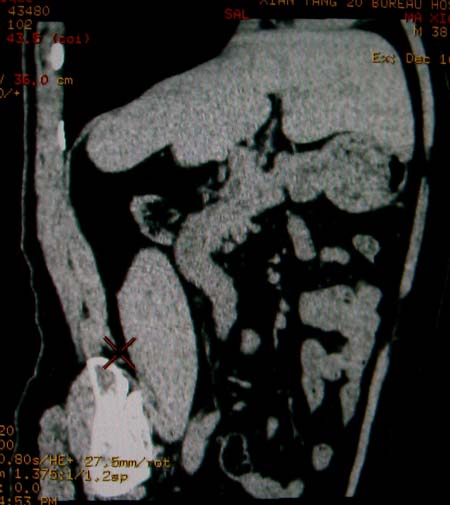

标题: CT17174:M38Y,体检超声提示右肾发育不良,病人无明显不适 [打印本页]

标题: CT17174:M38Y,体检超声提示右肾发育不良,病人无明显不适

右肾发育不良;考虑左肾下极血管平滑肌脂肪瘤可能,建议增强。

1)左肾下极占位性病变,不排除肾癌可能;建议行进一步检查。2)右肾发育不良。

左肾下极占位性病变,不排除肾癌可能;建议增强及明确内部组织ct值。右肾发育不良。

右肾发育不良。左肾代偿。左肾下极占位,性质待定,建议强化。

右肾发育不良。左肾下极囊实性占位,建议增强。